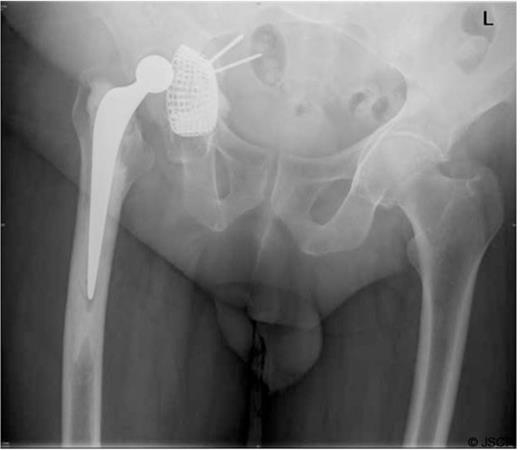

To avoid thrombus escaping from the iliac vein at the time of revision, a vena cava filter was inserted from the contralateral femoral vein (Figure 3).

Inferior vena cava (IVC) filter inserted prior to revision surgery